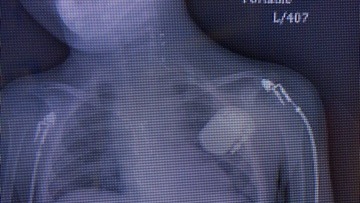

Everything was great, until at 1 year old he started to vomit. He was admitted at the hospital for dehydration but something was still wrong. When they took an x-ray of his abdomen they noticed that his heart was huge. He was immediately transferred to the ICU because he had dilated cardiomyopathy.

In March 2017, he had his first open heart surgery. He had to be connected to a Ventricular Assist Device called the Berlin Heart. The Berlin Heart is a pump that works as an artificial heart, providing the blood flow needed to the whole body and organs, and taking away all the work from the damaged heart.

Unfortunately, even though Pedrito´s heart condition was getting better, one week after being removed from the Berlin Heart he was submitted to various open heart surgeries because the doctors found a large infection in the chest wound. This infection passed through the sternum and infected the membrane surrounding the heart.

After 17 days with his chest open, the doctors were able to get rid of the bacteria. Because the infection reached the sternum they had to remove almost all of it, and to be able to close the chest they had to lift his pectoral muscles and overlap them to give support and protection to the chest. Pedrito then had to spend two weeks without being able to move his arms to allow the surgery to heal completely.